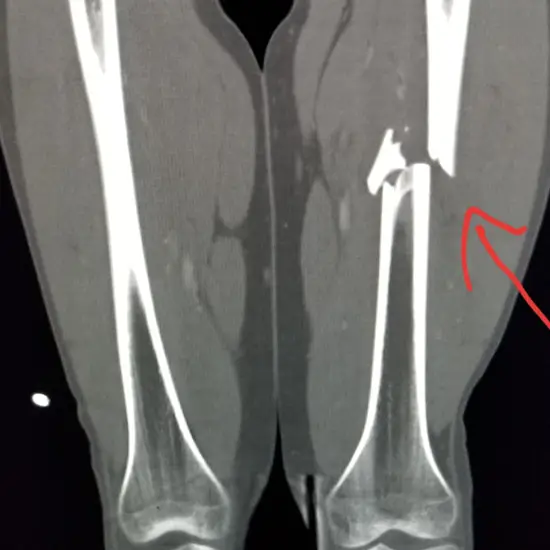

CECT Left Thigh is an imaging scan performed on the left thigh. It evaluates the Left thigh for abnormalities, fractures, infection, abnormal bone growth etc. The radiologist will inject you with a special dye (contrast media) before the scan. This scan is used to assess the thigh bone and its surrounding tissues for the problems.

Doctors recommend CECT left Thigh to evaluate the left thigh bone and its surrounding tissues for fractures, infection, inflammation, abnormal growth, unexplained pain etc.

CECT Thigh is a diagnostic imaging procedure that is conducted using radiation and contrast medium. The scan images produced help your doctor to evaluate the problems or conditions associated with the thigh including any fracture, abnormality, infection, abnormal growth of the bone etc.

CECT scan for the thigh is used to evaluate the structures present in the thigh area and its surrounding. the scan can help diagnose infections, fractures, abnormal growth, inflammation, or unexplained pain, etc.

A CT scan can be used with and without contrast for the thigh and aids in finding the cause of pain that can occur due to abscess, broken bone, infection, tumors, and masses. It can also be used in cases of examining the scar tissues after surgery, to diagnose arthritis, difficulty in walking, or swelling.